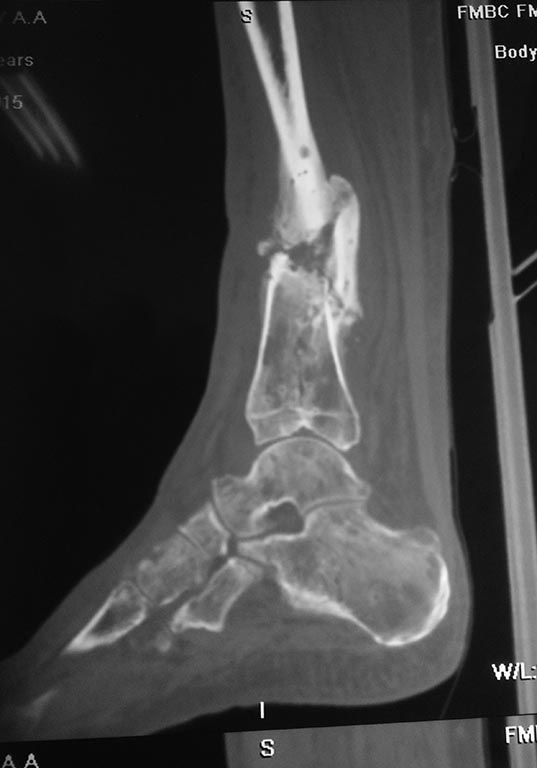

Небольшое уточнение: оперирован 1 августа, в ноябре снята база со стопы,

в конце декабря демонтаж аппарата. Показания к снятию аппарата-

заключение рентгенолога - консолидирующийся перелом, отсутствие

патологической подвижности. Рана заживала около 3 -х месяцев условно

первичным натяжением. Так как нет КТ руководствовались в основном

рентген снимками.

Снимки при поступлении, спустя 2,5 месяца. Рентген снимки после снятия

аппарата в архиве пришлю позже. Осылаю КТ от апреля.

Имя     : CT1.jpg

Тип     : image/jpeg

Размер  : 50937 байтов

Описание: отсутствует

Url     : http://weborto.net:8080/pipermail/ortho/attachments/20150601/e773a7a0/attachment-0007.jpg